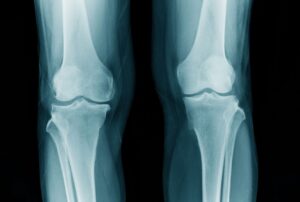

X脚とは、立ったときに両膝が内側に寄り、膝同士がくっつく姿勢を指します。

見た目の印象だけでなく、膝や足首、股関節、腰への負担が大きく、

放置すると膝痛や腰痛、O脚との混在、外反母趾などを引き起こすこともあります。

※図のように膝が内側に入り、足首が外側に開くのがX脚の特徴です。